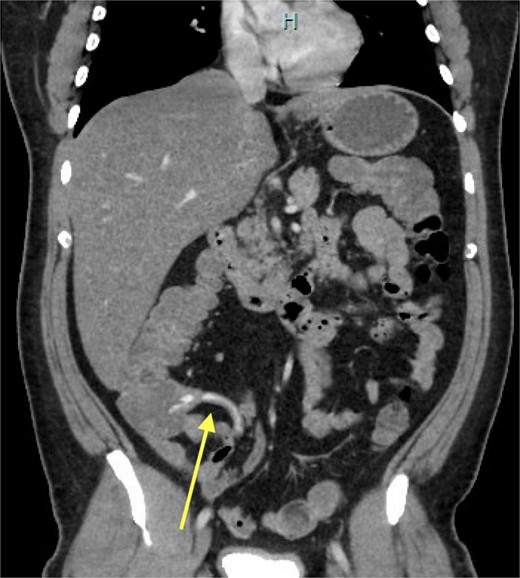

On Day 1 of admission, his haemoglobin count continued to drop to 89 g/L despite further transfusions and a normal gastroscopy. Repeat CTA performed at the time of another episode of large volume haematochezia demonstrated contrast extravasation arising from the appendix on the arterial phase, with pooling and spillage of contrast into the caecum on the subsequent phases, consistent with active haemorrhage within the appendix (Fig. 1). No overt appendiceal or caecal mass was seen. After discussion with the interventional radiologist, we decided not to pursue endovascular management. The patient was further resuscitated and preceded to a diagnostic laparoscopy. The appendix appeared healthy with neither overt masses nor signs of peritoneal disease. The appendiceal artery was controlled by endoclips, and the decision was made to perform a limited stapled caecectomy to incorporate the entire base of the appendix.

CT-angiogram, late arterial phase. Coronal CT slice showing contrast extravasation into the appendiceal lumen and spillage into the caecum.